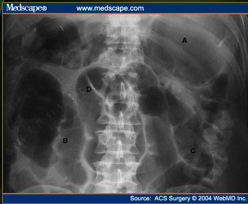

What does the following show?

Label A-D

Post-operative ileus

A: massive gastric distention

B: distended small bowel loops

C: air in colon & mild dilatation of sigmoid colon

D: Haustral fold in apex of sigmoid colon